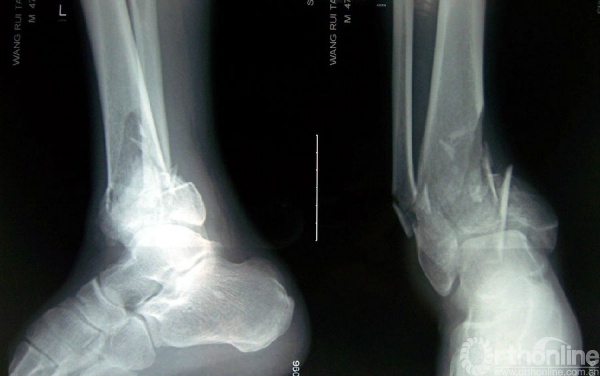

图3 男,35岁,左侧三柱Pilon骨折。

3a.术前正、侧位X线片示胫腓骨远端均为粉碎性骨折;

3b.水平面CT扫描可见属于内侧柱的内踝骨折块、属于中柱的前外侧和后唇骨折块;

3c.术后X线正侧位片示骨折解剖复位并于三柱上分别给予钢板固定,关节面平整。